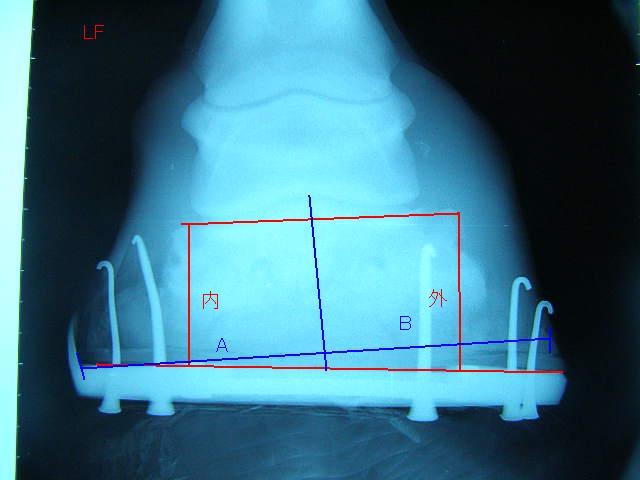

9月の右前肢

今回の右前肢

こちらも蟻洞がなくなりました。

順調に改善しているのが確認できて本当にホッとしました〜